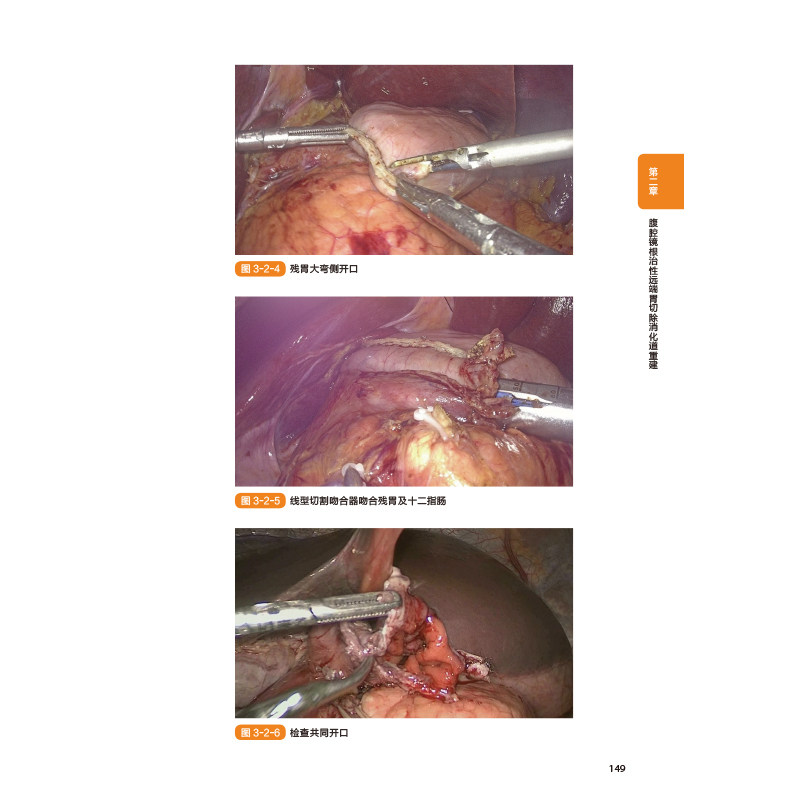

本书详细地介绍了胃的解剖及生理功能,翔实地阐述了腹腔镜胃癌领域中 新进展和 技术,从围手术期管理、腹腔镜器械和设备的应用、淋巴结清扫、消化道重建到术后并发症处理,作者都做了系统的描述。书中还配有色彩分明的解剖绘图、精美的手术照片,使读者能够充分了解腹腔镜胃癌手术的详细过程、操作技巧及相关临床要点,非常便于广大读者学习。此外,作者分享了其团队腹腔镜胃癌手术过程中的具体经验和体会,旨在为推动和普及腹腔镜胃癌手术规范化和精准化治疗做出贡献。